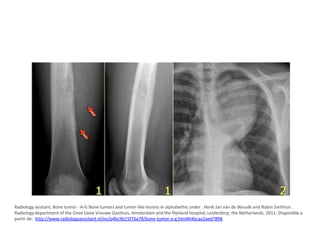

Sarcoma de Ewing

• Es un tumor maligno caracterizado por un

aspecto histológico uniforme constituido por

pequeñas células dispuestas en

conglomerados compactos con núcleos

redondos.

• Caracteristicas clinicas

– Dolor: síntoma mas temprano.

– Seguido de tumefacción

– Afecta a regiones diafisiarias y metafisiarias.

• Diagnostico por imágenes

– Destrucción ósea, asociada a reacción periostica en catafilas de

cebolla. Este signo no es patognomonico.

• Caracteristicas anatomo patologicas

– Población redondo celular con elementos de escaso citoplasma.

– Posee abundante glucogeno

– La neo formación de hueso o cartílago tumoral esta ausente:

metastatiza tempranamente en pulmones y otros huesos.

Osteosarcoma

Definición: Es un tumor maligno

caracterizado por la formación directa

de tejido óseo u osteoide por las

células tumorales.

«Es un tumor mesenquimal maligno

productor de hueso»

Características clínicas:

– Dolor en el sitio del tumor.

– Puede irradiarse a una articulación vecina

– Masa palpable: por crecimiento.

• Diagnostico por

imágenes

– Masa mixta, lítica.

– Márgenes poco

definidos.

– Triangulo de Codman.

– Reacción periostica (en

rayos de sol)